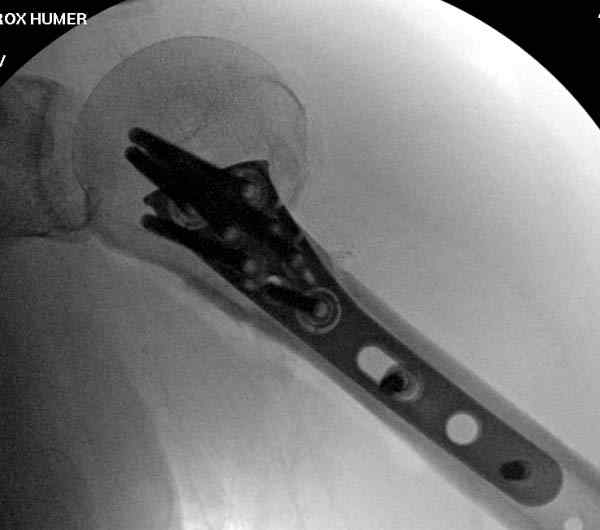

Здесь пример открытой репозиции 57 летнего с переломом плеча (1,2) смещение обнаружено на интероперационном снимке. При нормальной прямой проекция (3) угловое смещение обнаружили в аксиальной проекции (4)

После устранения смещения пластина установлена выше (5,6,7) и финальные снимки (8,9,10)

Подбор импланта тоже имеет значение, например многие импланты направлены для фиксации перелома без учета ротаторной манжетки. Предпочтительными являются низко сидящие полиаксиальные пластины, где верхние шурупы можно проводить под углом в 120 градусов. (11)